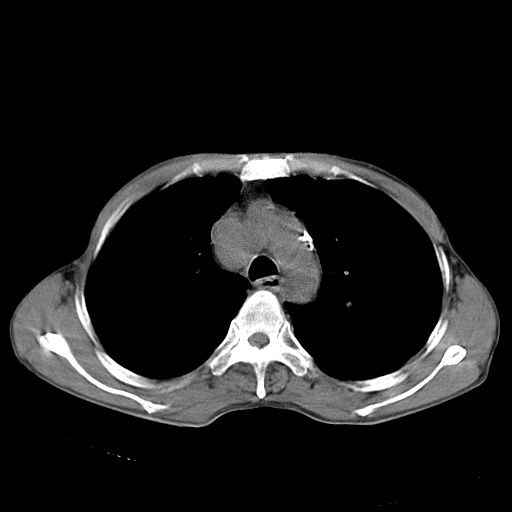

以下是引用苯小孩在2007-5-24 12:47:00的发言:[br]右侧肺门处不均匀密度软组织块影,远端肺组织见斑片模糊影,纵隔内淋巴结明显肿大,边界不清.<纵隔窗第12层面支气管内似见软组织结节>[br]考虑:1、右侧中央性肺癌并阻塞性肺炎并纵隔淋巴结转移可能性大.建议强化或纤支镜进一步检查.[br]2、隆突下淋巴结肿大/食道病变?请做鉴别检查.

以下是引用zhangzhongshou在2007-5-24 12:55:00的发言:[br]1、右肺中叶中心型肺癌并右肺门、隆突下、纵隔淋巴结转移。右肺中叶阻塞性肺炎。

以下是引用jw-830在2007-5-24 15:24:00的发言:[br][br] [br] 考虑右肺中央型肺癌并阻塞性炎症,右肺门及纵隔淋巴结转移。 [br] [br][br]